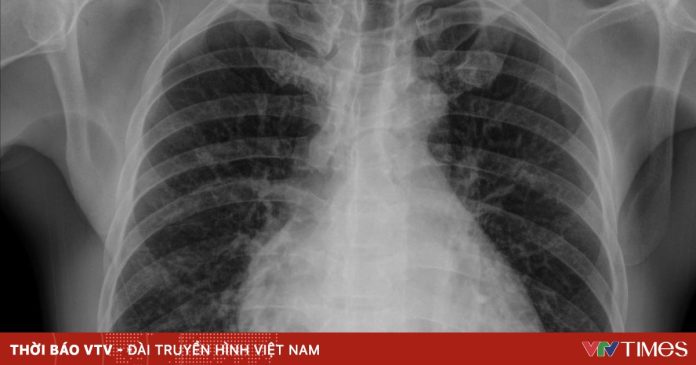

Trường hợp bệnh nhân C.Đ.C. (52 tuổi, Phú Thọ) nhập Bệnh viện Bạch Mai vì chảy máu mũi kéo dài. Trong quá trình điều trị bạch cầu cấp dòng tủy, người bệnh được truyền huyết tương và sau khoảng 20 phút, xuất hiện khó thở, SpO2 giảm, nghe phổi có ran ẩm hai bên. Kết quả chụp CT cho thấy phù phổi cấp, được xác định là quá tải tuần hoàn liên quan truyền máu (TACO). Bệnh nhân được xử trí kịp thời và cải thiện.

Các nghiên cứu quốc tế cho thấy biến chứng phổi sau truyền máu không hề hiếm. Tại Bệnh viện Đại học California (2012-2022), trong hơn 573.000 lượt truyền, có 102 ca TACO, tương đương 1/500 người truyền. CDC Hoa Kỳ ước tính tần suất TACO từ 1-11% tùy nhóm bệnh nhân.

Theo PGS.TS Nguyễn Tuấn Tùng – Phó Giám đốc Bệnh viện Bạch Mai, tổn thương phổi là nguyên nhân tử vong hàng đầu trong tai biến truyền máu và có thể xảy ra ngay ở đơn vị đầu tiên. Vì vậy, việc giám sát sát sao từng ca truyền là cực kỳ quan trọng.